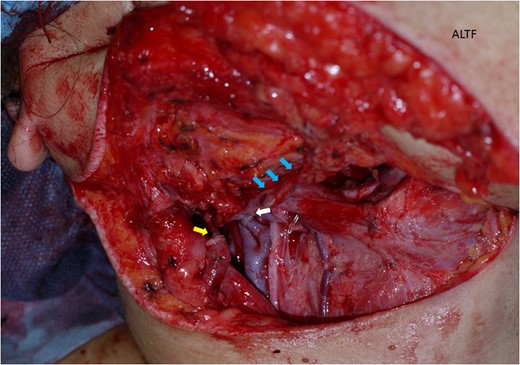

The surgical treatment for this patient involved tracheostomy, hemi-glossectomy and right-sided selective neck dissection when the patient was in her 28th week of pregnancy. Throughout the surgery, the patient was given a continuous intravenous infusion of ritodrine hydrochloride (100 mg in 500 ml) in order to provide tocolysis and prevent premature labour. A tracheotomy was preformed and the patient underwent a modified rapid sequence induction using fentanyl, thiopentone and rocuronium bromide. Anaesthesia was maintained with sevoflurane. A continuous fentanyl infusion provided analgesia and paralysis was maintained with boluses of atracurium besylate. Obstetricians were standing by for unexpected delivery. A cardiotocograph was used to monitor the foetus. The tissue defect was reconstructed with an antero-lateral thigh flap (Figs 3–5). The descending branch of lateral circumflex femoral artery was anastomosed to her right facial artery. One comitant vein was anastomosed to her external jugular vein in end-to-end fashion with a 2.5 mm microvascular anastomotic device. The other comitant vein was anastomosed in the same way to a branch of internal jugular vein with a 2.0 mm coupler. Heparin-saline solution (5000 units in 100 ml) was used to irrigate the anastomotic sites. Systemic heparin administration was not done during the operation. Lidocaine (2%) was used as vasodilator. Prostaglandin E1 was not administered. The operation took 7 h and 40 min. Blood loss was estimated to be 340 ml and no blood transfusion was required. Throughout the operation, no remarkable incidents were noted on the electronic foetal monitoring.

The antero-lateral thigh flap (ALTF) was pulled through, trimmed and sutured to fill the tongue defect.